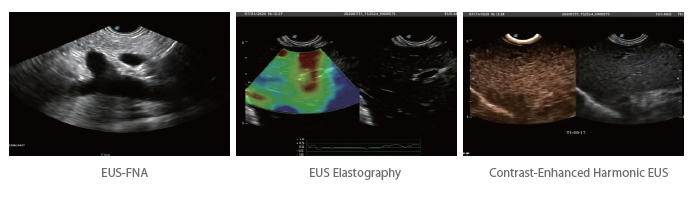

- Усі стандартні методи та доплерівська технологія

- УЗД з контрастним підсиленням та еластографія УЗД